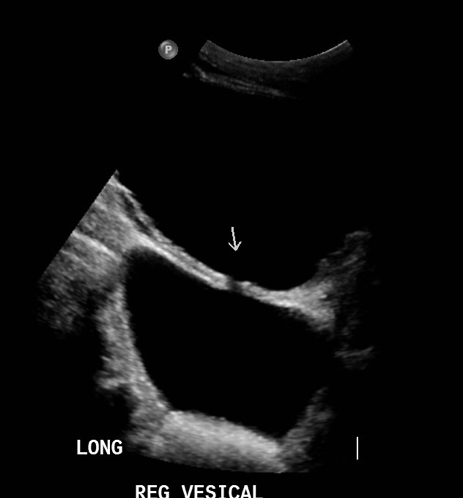

Leve irregularidad de bordes vesicales. En su lumen, se observan múltiples pequeños cálculos móviles a los cambios de posición, que no obstruyen unión ureterovesical distal. Se observa además gran divertículo vesical con cuello que demuestra flujo urinario bidireccional, en donde también se observan múltiples pequeños cálculos móviles a los cambios de posición.

*Se mide pre y post micción a nivel de vejiga, vejiga + diverticulo y diverticulo.